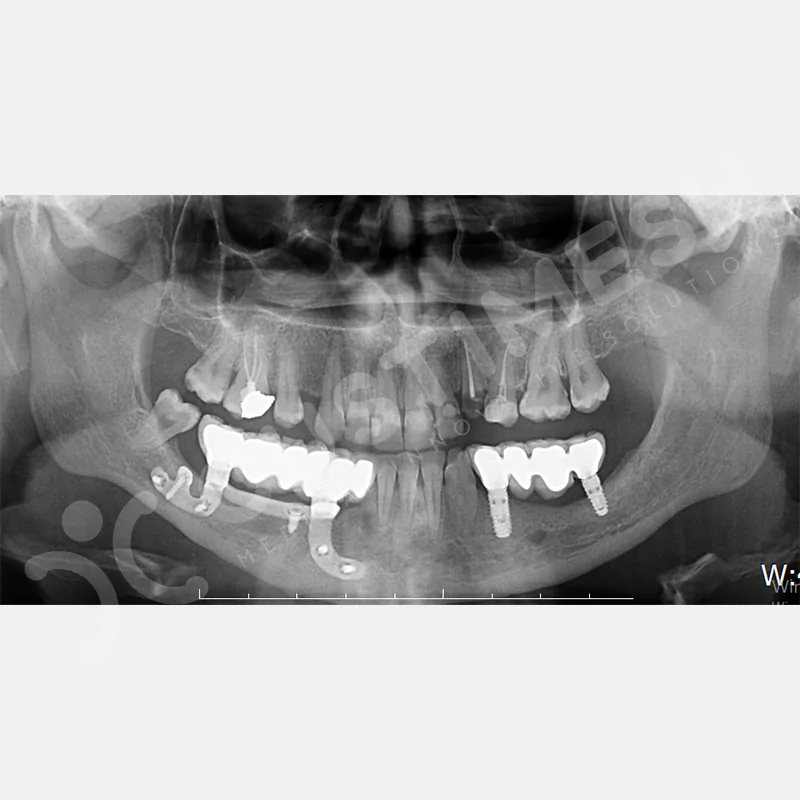

Modern diş hekimliğinde, çene gelişimini tamamlamamış veya ciddi kemik kaybı yaşayan hastalar için kişiye özel titanyum implantlar ile çözüm bulunmaktadır. CAD/CAM teknolojisi ve lazer sinterleme yöntemiyle üretilen bu implantlar, hastanın bireysel anatomik yapısına tam uyum sağlayarak geleneksel implantların uygulanamadığı vakalarda mükemmel bir alternatif oluşturmaktadır. Özellikle ileri derecede kemik kaybı olan hastalar için geliştirilen subperiosteal implantlar, periostun altına yerleştirilerek minimal invaziv bir yaklaşım sunarken, bilgisayarlı tomografi verileri ve sonlu eleman analizleriyle optimize edilmiş tasarımları sayesinde hem estetik hem de fonksiyonel sonuçlar garanti etmektedir. Bu yenilikçi teknoloji, tek seansta implant ve protez uygulamasına imkan vererek hastaların aynı gün doğal gülüşlerine kavuşmalarını sağlarken, kemik greftleme gibi ek işlem ihtiyacını ortadan kaldırarak cerrahi süreci büyük ölçüde kolaylaştırmaktadır. Kişiye özel tasarımı ve üstün biyouyumluluğu sayesinde, daha önce tedavisi mümkün görülmeyen kompleks vakalarda bile başarılı sonuçlar sunan bu implantlar, modern diş hekimliğinde yeni bir çağ açarak hastaların yaşam kalitesini artırmayı hedeflemektedir.

Hekim tarafından onaylanan Custiplate, 3 boyutlu yazıcı teknolojisi kullanılarak Grade 23 (Ti6Al4V) Medikal Titanyum Alaşımından üretilir. - KARGO

VAKA 3